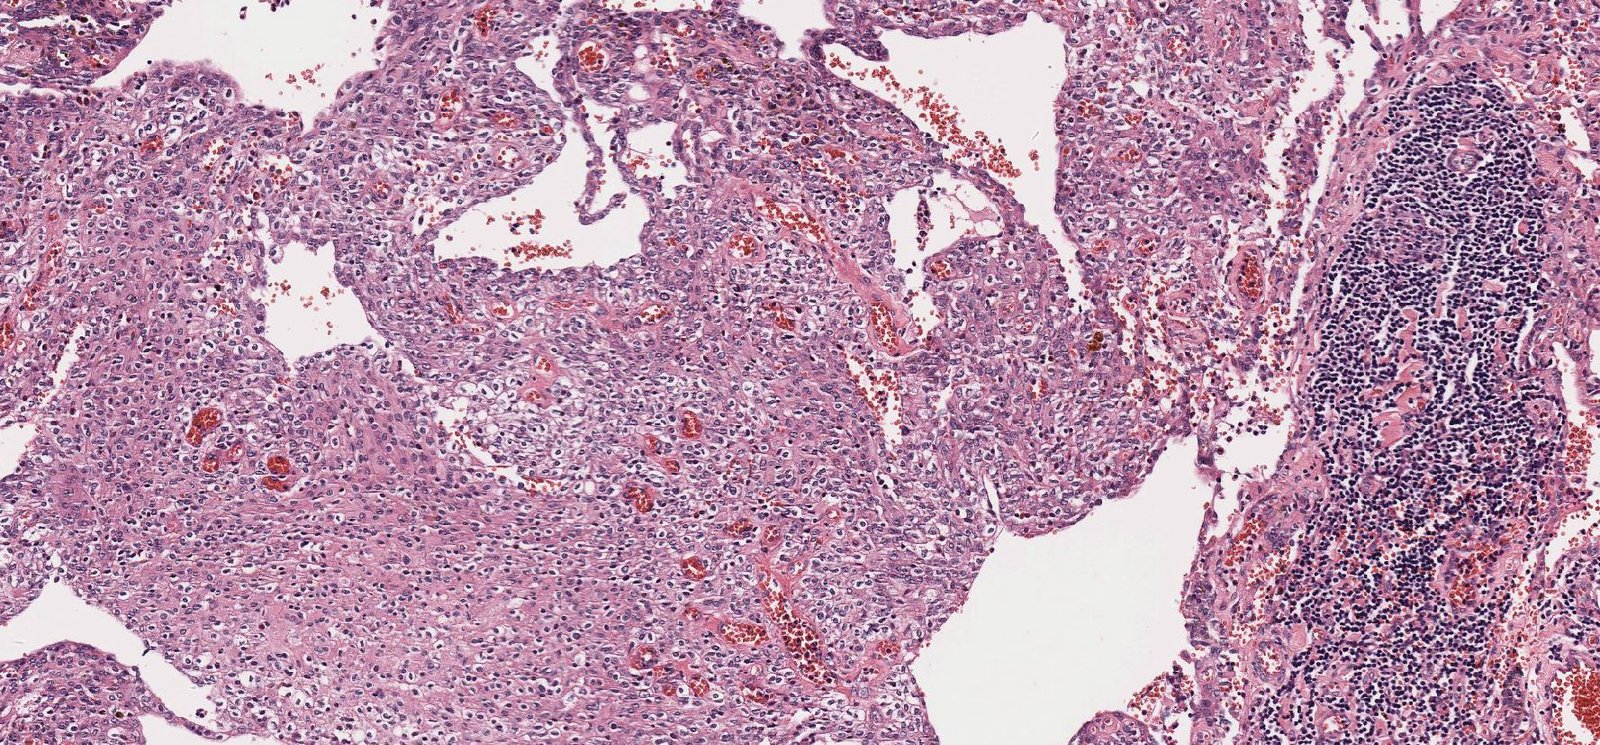

Case: NeckMass

Final Diagnosis: